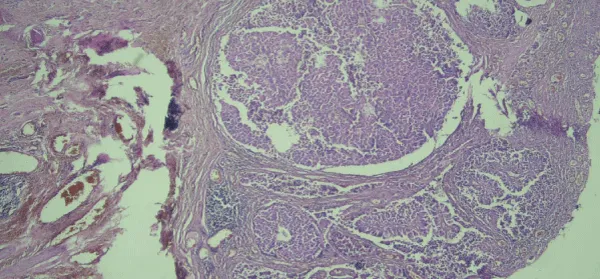

A 62-years old female was in natural menopause for 14 years. She was referred to oncology department of Ghaem hospital, Mashhad University of Medical Sciences in July 2016. She suffered of painful vulvar lesion with severe purities for 4 years. In examination, an erythematous and exfoliated lesion of the right major and minor labia extend to anus was detected. It also extended up to the clitoris, but did not invade to external urethral meatus. She had history of using recurrent topical corticosteroid. The result of the biopsy was PDV with full-thickness involvement (Figure 1). In investigations, she had persistent hematuria. Screened for any associated underlying malignancies including breast examination, mammography, pelvic and abdominal ultrasonography, colonoscopy, and chest X-ray were normal. Pelvic CT scan was revealed irregularity of the posterior wall of the bladder. Results of cystoscopy biopsy determined low-grade urothelial carcinoma (Figure 2). As an associated malignancy, she underwent successful radical cystectomy. In addition, treatment proposed for the vulvar lesion topical imiquimod 5% cream to be applied every other day after confirming of bladder carcinoma. After 6 weeks of therapy, the patient is free of disease and now is under serial follow-up.